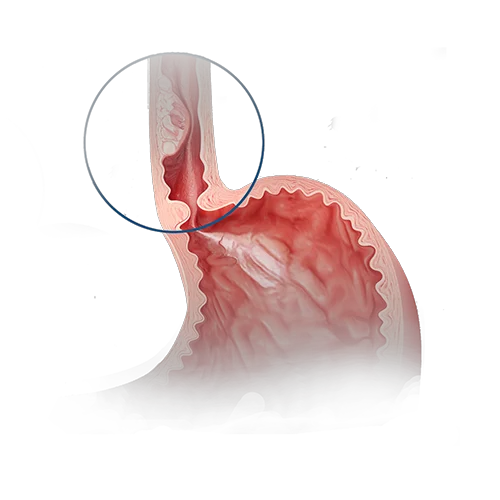

食管癌是一种恶性肿瘤。其发生源于食管黏膜细胞的异常突变,随着时间的推移,疾病不仅会扩散至食管壁的各个层次,还会沿着食管蔓延。肿瘤逐渐阻塞食管腔,阻碍食物通过,导致患者出现消瘦,严重时甚至死亡。

- 胸段食管癌.

- 食管下三分之一部位癌.